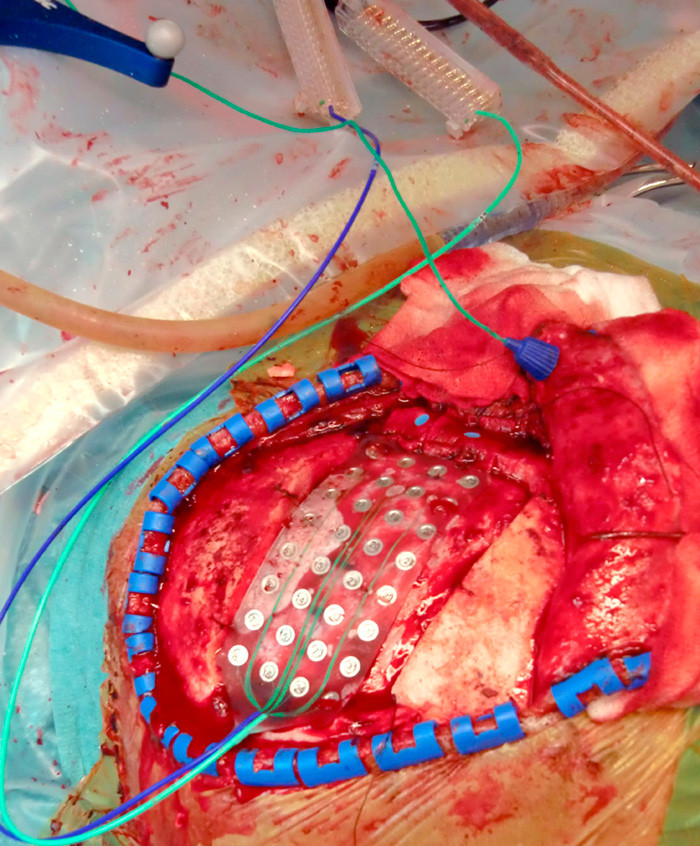

The images show an intra-operative assessment of the primary motor cortex of the patient. The assessment is performed using MRI and neuronavigation, somatosensory evoked potentials (SSEP) and electromyography (EMG). The aim of the surgery was to implant permanent electrodes over relevant areas of the primary motor cortex to relieve chronic and medically intractable pain.